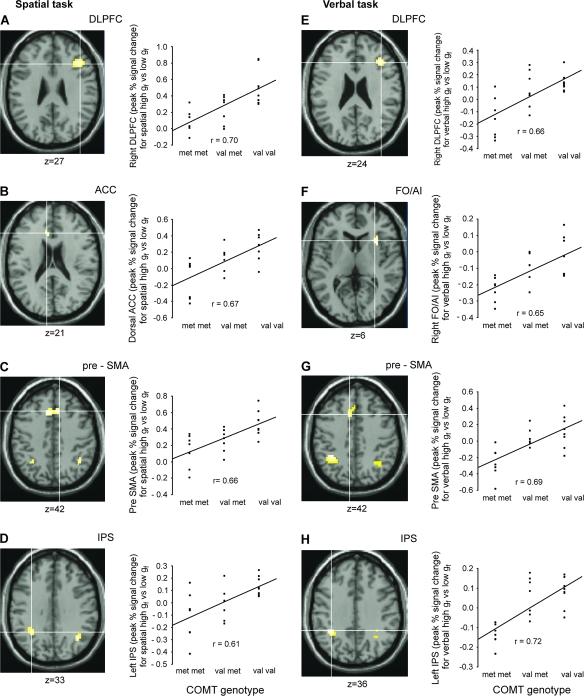

Fluid intelligence (g(f)) influences performance across many cognitive domains. It is affected by both genetic and environmental factors. Tasks tapping g(f) activate a network of brain regions including the lateral prefrontal cortex (LPFC), the presupplementary motor area/anterior cingulate cortex (pre-SMA/ACC), and the intraparietal sulcus (IPS). In line with the "intermediate phenotype" approach, we assessed effects of a polymorphism (val(158)met) in the catechol-O-methyltransferase (COMT) gene on activity within this network and on actual task performance during spatial and verbal g(f) tasks. COMT regulates catecholaminergic signaling in prefrontal cortex. The val(158) allele is associated with higher COMT activity than the met(158) allele. Twenty-two volunteers genotyped for the COMT val(158)met polymorphism completed high and low g(f) versions of spatial and verbal problem-solving tasks. Our results showed a positive effect of COMT val allele load upon the blood oxygen level-dependent response in LPFC, pre-SMA/ACC, and IPS during high g(f) versus low g(f) task performance in both spatial and verbal domains. These results indicate an influence of the COMT val(158)met polymorphism upon the neural circuitry supporting g(f). The behavioral effects of val allele load differed inside and outside the scanner, consistent with contextual modulation of the relation between COMT val(158)met genotype and g(f) task performance.

流体智力(g(f))影响着许多认知领域的表现。它受到遗传和环境因素的双重影响。涉及g(f)的任务会激活包括外侧前额叶皮质(LPFC)、辅助运动区/前扣带回皮质(pre-SMA/ACC)和顶内沟(IPS)在内的脑区网络。根据“中间表型”方法,我们评估了儿茶酚-O-甲基转移酶(COMT)基因中的一个多态性(val(158)met)对该网络内活动以及在空间和语言g(f)任务期间实际任务表现的影响。COMT调节前额叶皮质中的儿茶酚胺能信号传导。val(158)等位基因比met(158)等位基因与更高的COMT活性相关。对COMT val(158)met多态性进行基因分型的22名志愿者完成了空间和语言问题解决任务的高g(f)版本和低g(f)版本。我们的结果表明,在空间和语言领域的高g(f)与低g(f)任务表现中,COMT val等位基因负荷对LPFC、pre-SMA/ACC和IPS中血氧水平依赖反应有积极影响。这些结果表明COMT val(158)met多态性对支持g(f)的神经回路有影响。val等位基因负荷的行为效应在扫描仪内外有所不同,这与COMT val(158)met基因型与g(f)任务表现之间关系的情境调节一致。